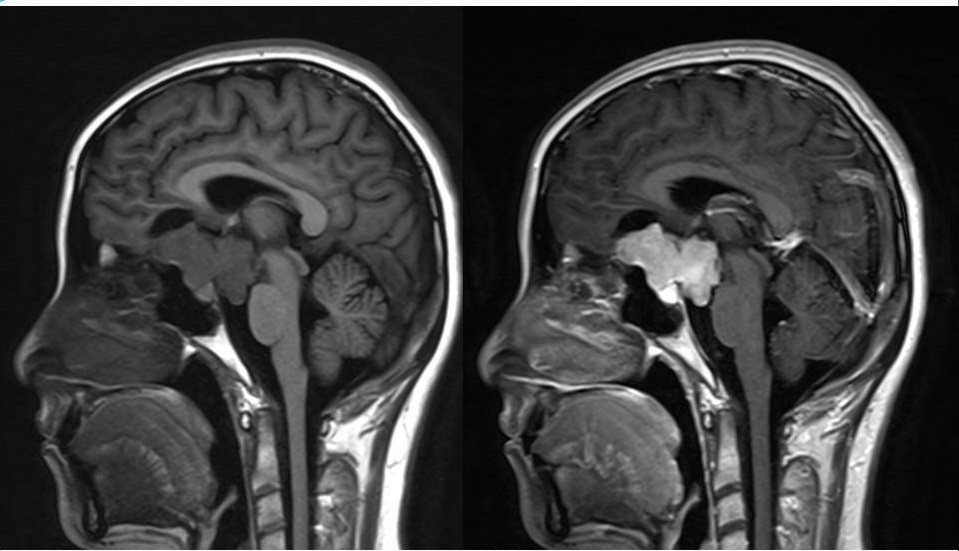

2.MR检查显示肿瘤位于鞍区,分叶状生长,呈稍长T2、稍长T1异常信号影,边界清楚,内部信号不均匀,其内可见“微囊”状异常信号影,视交叉受压上抬,DWI呈等或略高信号影,注药后呈不均匀明显强化;

4.重点观察冠状位:病变源于垂体偏左侧,与垂体界限不清楚,肿瘤偏右侧可见垂体与肿瘤之间裂隙,造成矢状位平扫及强化后误认为正常垂体存在,从而首先除外了垂体瘤,导致误诊;